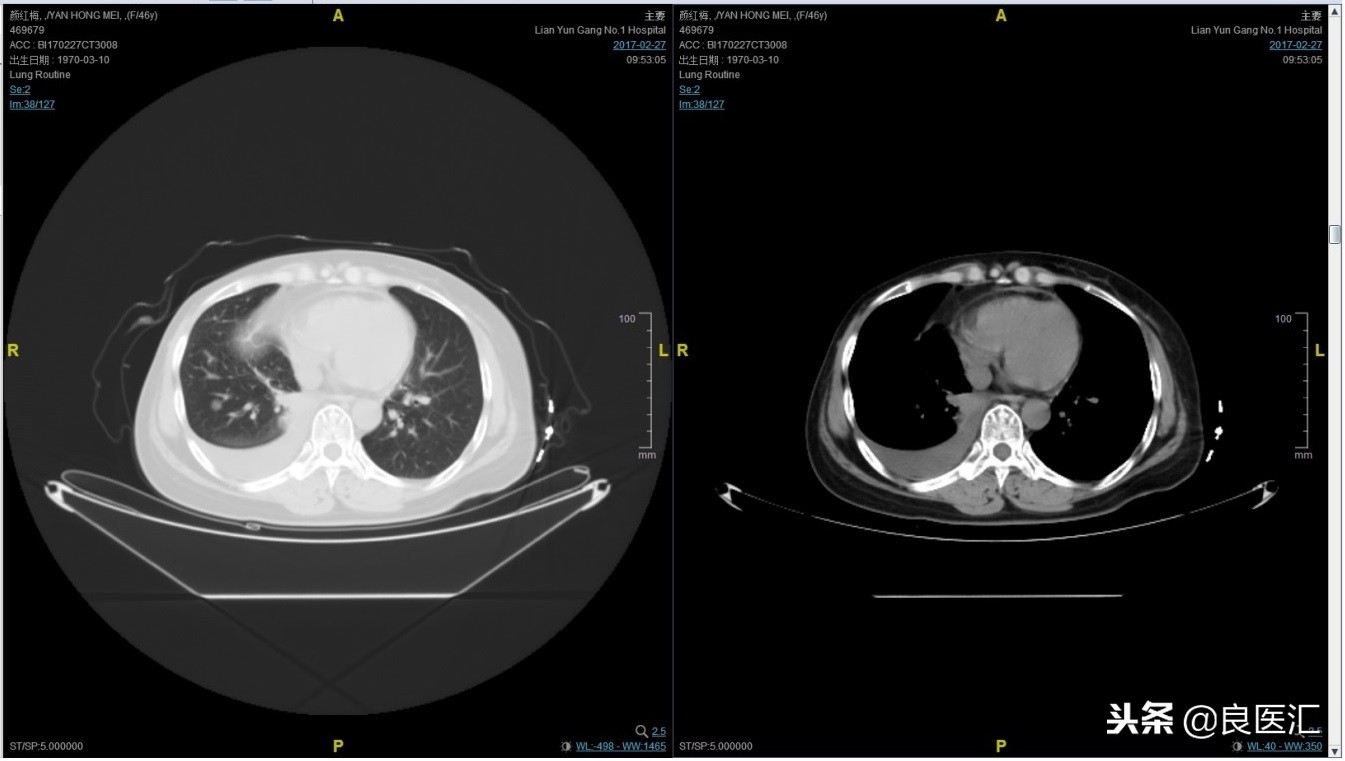

2017-02-27患者因气喘胸闷再次就诊。患者肺部病灶进展,同时出现肝脏转移。再次给予曲妥珠单抗+长春瑞滨化疗一周期,效果不佳,推荐换用TKI治疗,患者放弃治疗。PFS3=12个月。

总结